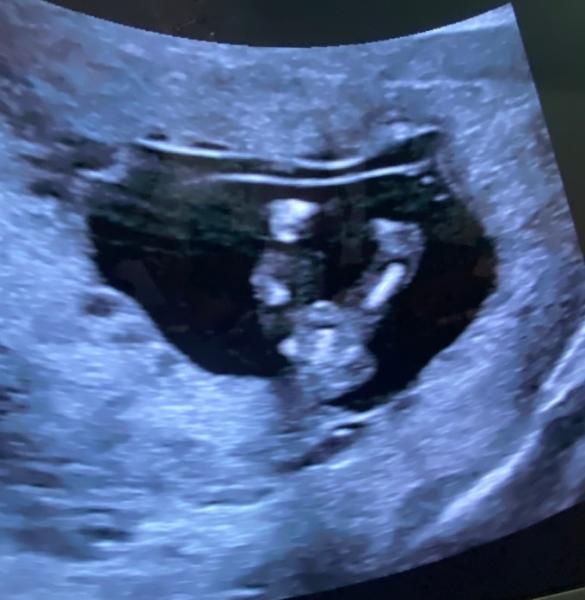

Hallo ihr Lieben, was meint Ihr? Junge oder Mädchen? Bild von heute 12+3 SSW.

Bin zwar kein Gynäkologe, laut NUB Theorie würde ich aber auf ein Mädchen tippen

Ich sage Mädchen :)

Hallo aus dem Februar Bus;) Ich würde auch Mädchen sagen Liebe Grüße